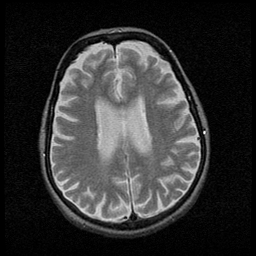

Huntington's Chorea, MR -- Slice #13